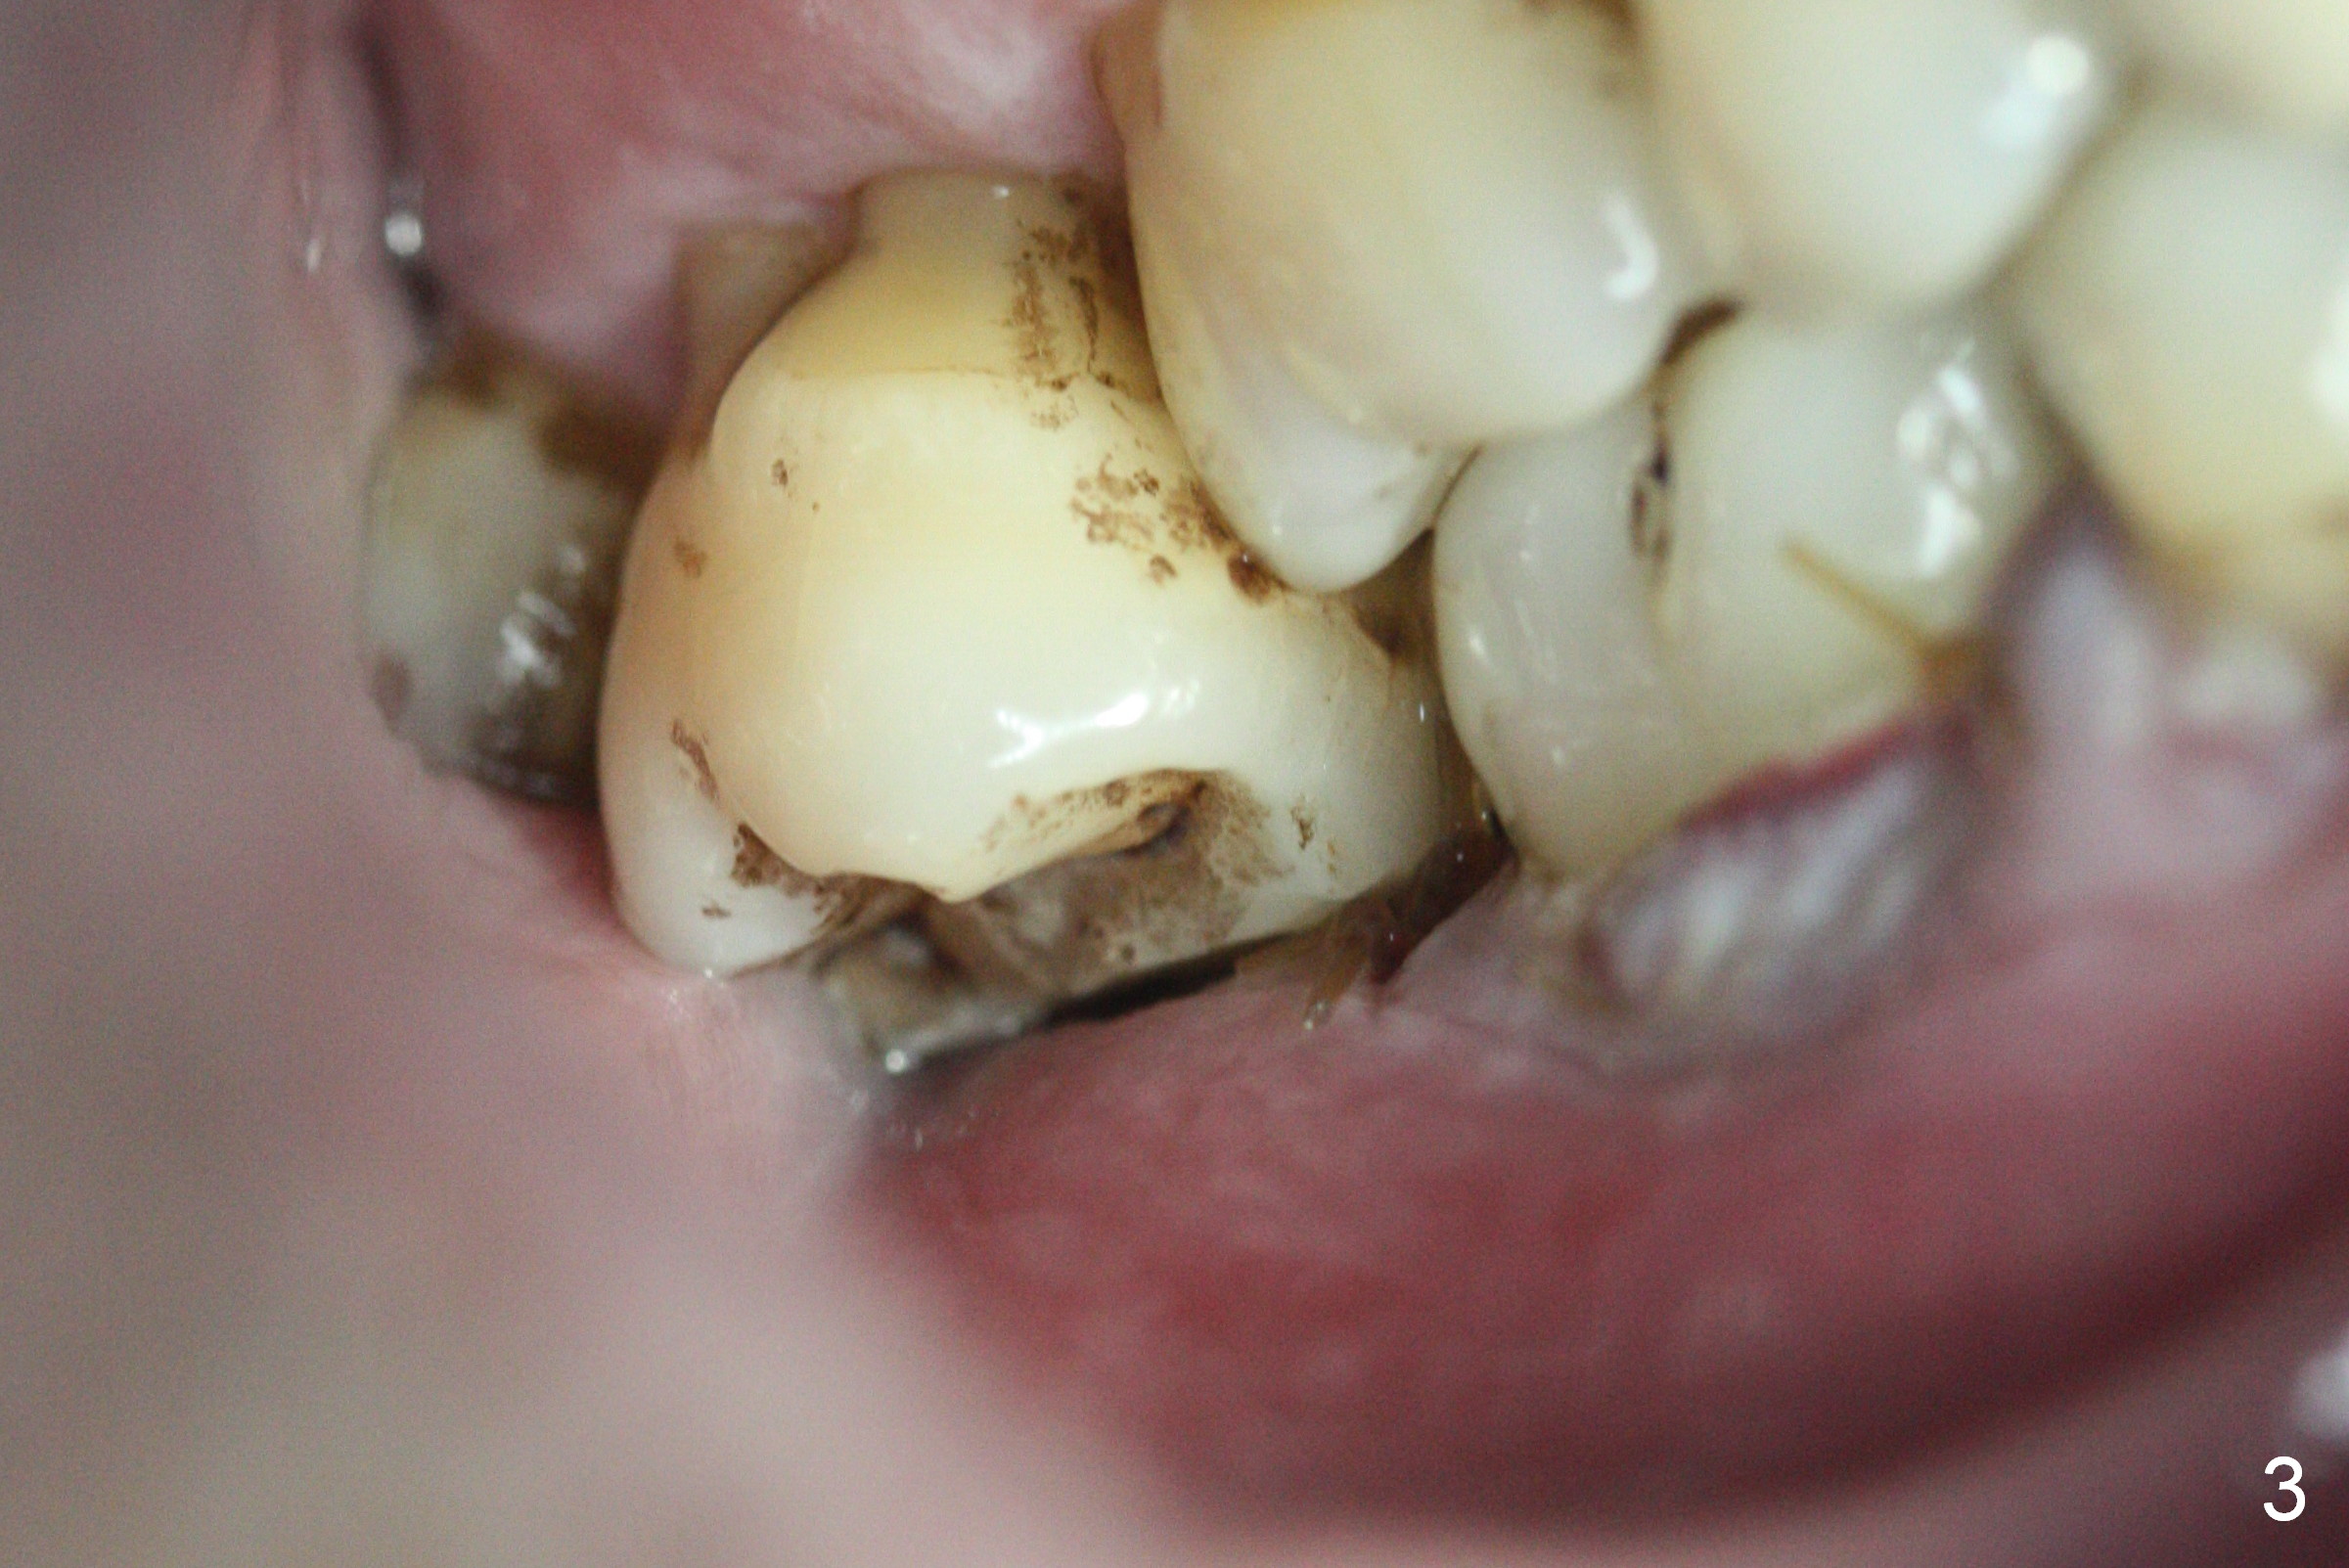

Two days post #31 implant placement, the patient returns for orthodontic intrusion of the tooth #2 with mini-implants (Fig.1). The palatal cusps have been trimmed (Fig.2 ^), since they almost contact a healing abutment at #31(*, Fig.3). Two mini-implants are to be placed mesiobuccal and distopalatal to the affected tooth. After minimal injection of Lidocaine, a 1.6x6 mm Tomas implant is placed in full length mesially (Fig.4), while the other (1.6x8 mm) half way (Fig.4). Following change in implant site mesially (Fig.6 >), the implant is half inserted (Fig.5). It appears that the tip of the distal implant is toward the tooth #1 (Fig.5). After withdrawing the implant partially, it is re-directed to apparently ideal trajectory (Fig.7). Ideally the mesial implant (Fig.8) should have been placed partially initially (Fig.4,5,7) so that the trajectory could have been able to be changed.

The buccal implant becomes loose in 2-3 months. When the wound heals (Fig.9 <), a 1.6x`10 mm implant is placed with the help of PAs for trajectory (Fig.10,11) and in the nonkeratinized gingiva (higher, the crestal bone may have been traumatized by previous implant placement, Fig.12). Two months later, the tooth #2 is partially intruded (Fig.13). A provisional (Fig.14 P) is fabricated in the osteointegrated implant at #31 with supraocclusion so that the remaining dentition has no occlusal contact (*). The periodontally compromised tooth #2 becomes in buccoversion in 2 months. The provisional is removed, while a lingual button is placed in the buccal surface of the tooth #2 (Fig.15). With power chain attached to the lingual mini-implant, the tooth #2 is lingualized in 2 months. The provisional and the implants are reused for final intrusion (Fig.16). The treatment is nearly 11 months. The buccal implant, although placed in the movable mucosa, remains stable and healthy (Fig.17). The tooth #1, as a guiding plane (to prevent #2 from distalization during intrusion), is not extracted after intrusion is completed.